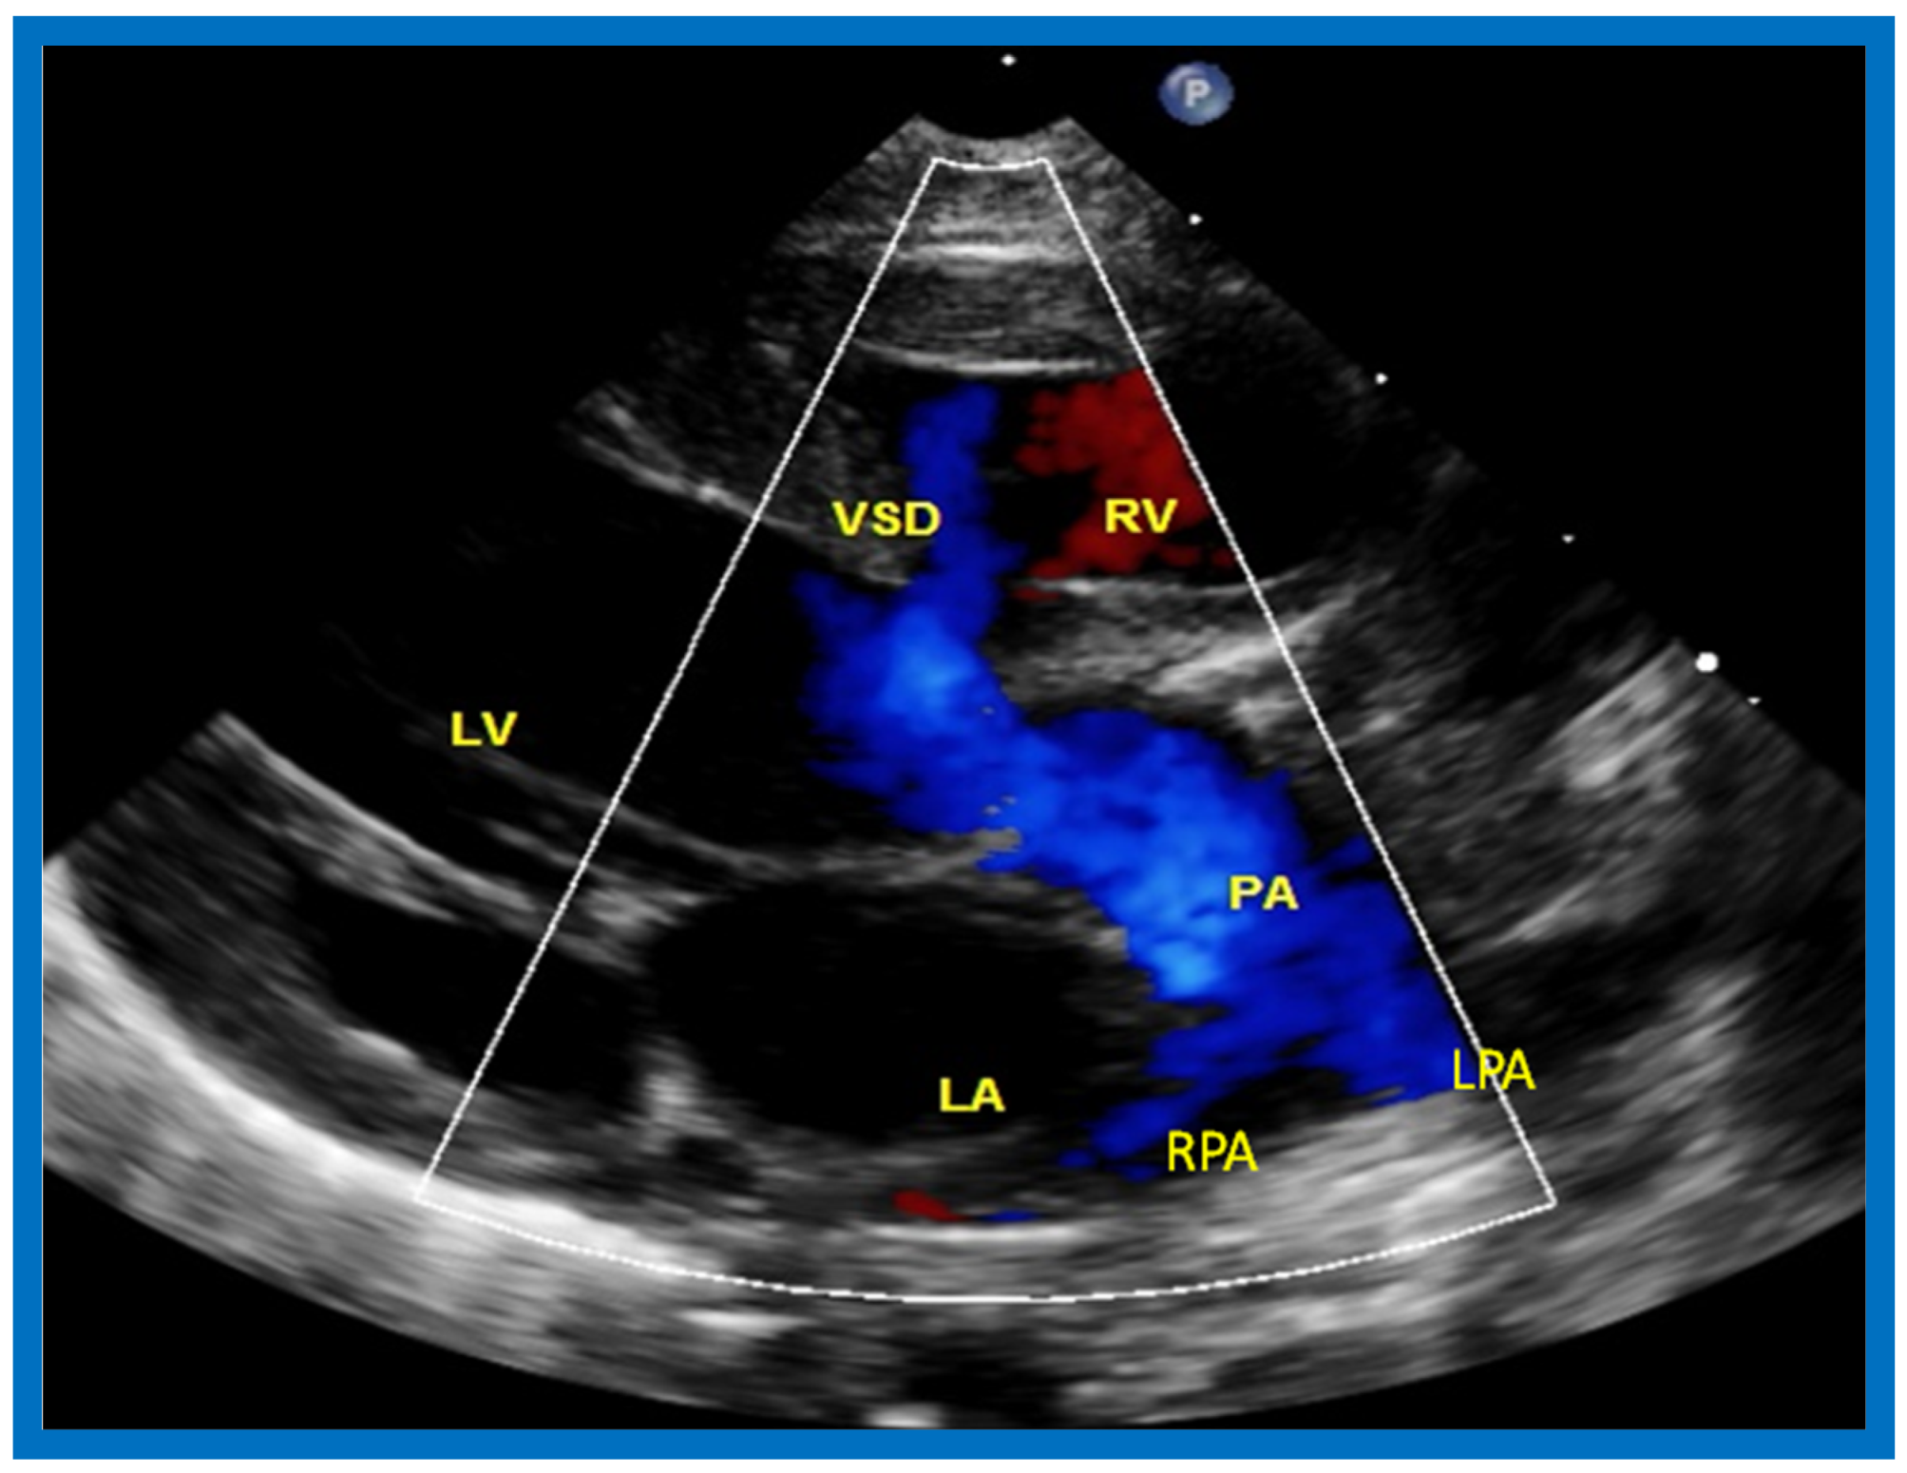

The relationship of the great arteries is examined next in order to classify them into various types [41]. The relationship of the great arteries is established by following the vessels arising from the ventricles until pulmonary bifurcation or aortic arch. In Type I patients with normally related great arteries, the aorta arises from the LV (Figure 20), while in Type II patients with transposition of the great arteries, the PA arises from the LV (Figure 21 and Figure 22). In Type III patients, it may be little more difficult to assign the great artery relationship, and sometimes angiography is needed. In type IV with truncus arteriosus, the limited data [22] suggest that this can be done by echocardiography (Figure 23 and Figure 24).

Figure 22.

Selected video frame from precordial long axis view with color flow mapping of another neonate with tricuspid atresia and transposition of the great arteries illustrates the left atrium (LA), left ventricle (LV), a small right ventricle (RV) and a moderate sized ventricular septal defect (VSD). The vessel coming off of the LV bifurcates into left (LPA) and right (RPA) pulmonary arteries. Reproduced from Rao P.S. [39].

Then, the ventricular septum is evaluated; the ventricular septum is intact in most Type Ia cases. In children with Type I (normally related great arteries), the VSD supplies pulmonary blood flow (Figure 20) while in patients with Type II (transposition the great arteries), the VSD allows blood to flow into the systemic circuit (Figure 21 and Figure 22). In Type I patients, the VSD is demonstrated by 2D (Figure 20A) and the left to-right shunt across it by color (Figure 20B), pulsed and CW (Figure 20C) Doppler signals. Interrogation of the right ventricular outflow tract and pulmonary artery region is performed; peak Doppler flow velocity across the right ventricular outflow tract and pulmonary valve is helpful in identifying obstruction across these sites. The Doppler data from the VSD and RVOT are also helpful in estimating of pulmonary artery pressures. In these Type I babies, the 2D size of the VSD and the peak Doppler flow velocity across it are useful in quantifying the size of the VSD (Figure 20); the higher the VSD Doppler velocity, the smaller the defect. However, in patients with pulmonary hypertension, severe infundibular or valvar pulmonary stenosis, the VSD Doppler velocities do not reflect the size of the VSD. Barring these exceptions, right ventricular and pulmonary arterial pressure may be estimated using modified Bernoulli equation (RV/PA systolic pressure = systolic BP − 4V2).

In Type II patients, the VSD may be small, causing obstruction to blood flow to the systemic circuit; therefore, the size of the VSD should be ascertained by 2D (Figure 21 and Figure 22), color Doppler (Figure 22), pulsed (Figure 25) and CW Doppler, as necessary. In these Type II patients, the high VSD velocity is indicative of subaortic obstruction. Interrogation of left ventricular outflow and PA region may reveal pulmonary or subpulmonary stenosis; the higher the velocity, the more severe the obstruction. Study from suprasternal notch may show aortic coarctation (Figure 26), which is not uncommon in patients with the Type II anatomy.